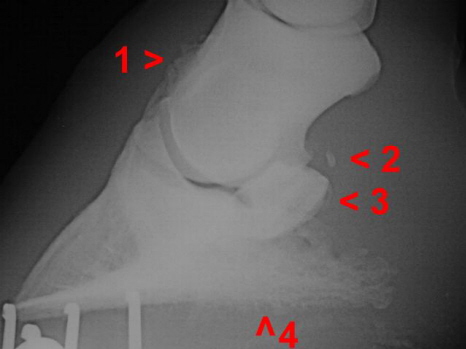

Arthrose Hufgelenk